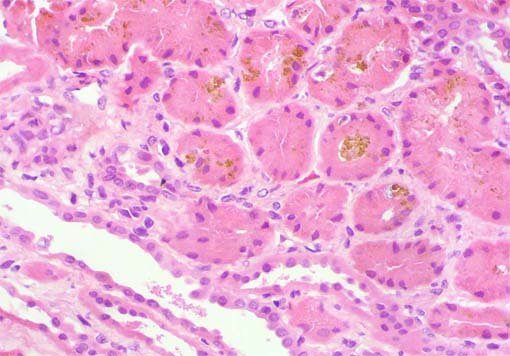

Figura 3.

H&E, X400.